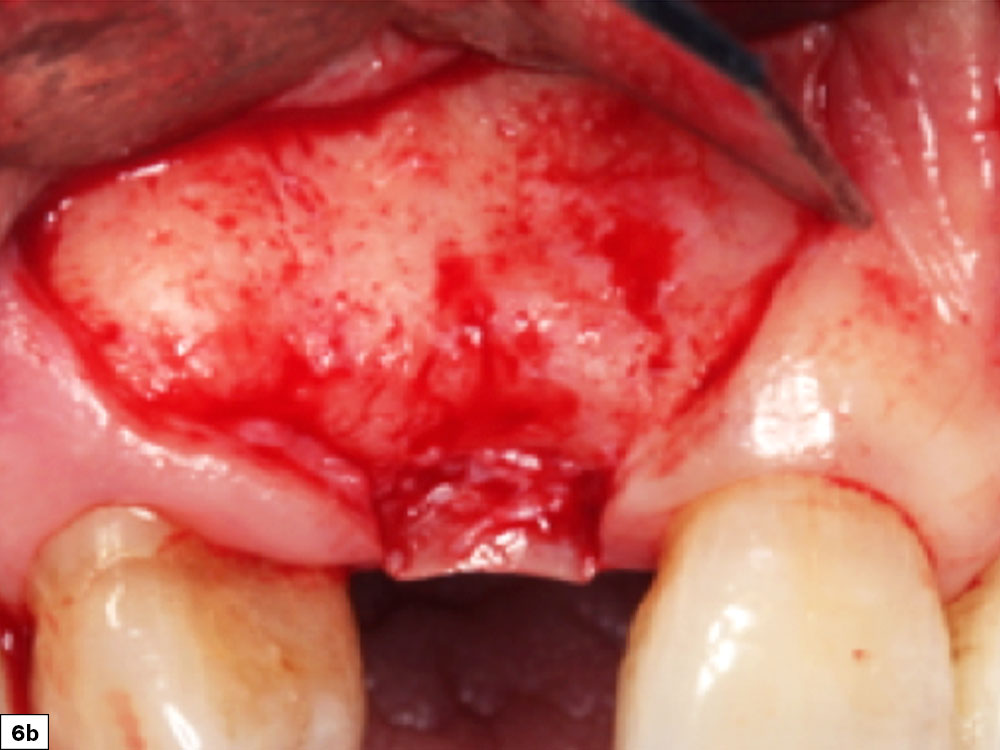

The coronal incision is usually positioned on the crest of the ridge, with a more palatal position if the amount of existing attached tissue is compromised. Vertical release incisions are made on the buccal surface and extend to the mucogingival junction. Broad-based incisions are important to prevent interruptions in the vascular supply to the flap and to allow for elevation, retraction, repositioning and suturing without tension. It is imperative that a continuous full-thickness incision be made on bone through the tissue and the periosteum. Incisions that are irregular may lead to maceration of the flap, which compromises the primary blood supply source (periosteal tissue layer). When incisions involve adjacent teeth, papillae-sparing incisions should be completed, leaving a minimum of 1 mm of the papilla intact (Figs. 6a, 6b).

Papillae-sparing incision maintains blood supply

Papillae-sparing incision prevents postoperative tissue recession

Figures 6a, 6b: Papillae-sparing incision depicting a broad-based design that maintains blood supply and prevents postoperative tissue recession.